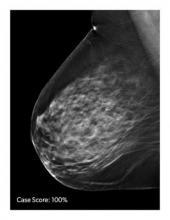

AI is also helping simplify complex tasks and help reduce the reading time on involved exams. One example of this is in 3-D breast tomosythesis with hundreds of images, which is rapidly replacing 2-D mammography, which only produces 4 images. Another example is automated image reconstruction algorithms to significantly reduce manual work. AI also is now being integrated directly into several vendors' imaging systems to speed workflow and improve image quality.